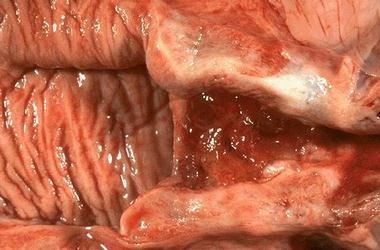

阴道是由粘膜、肌层和外膜组成的肌性管道,富伸展性,连接子宫和外生殖器,它是女性的交接器官,也是排出月经和娩出胎儿的管道。阴道常处天前后壁相接触的塌陷状态